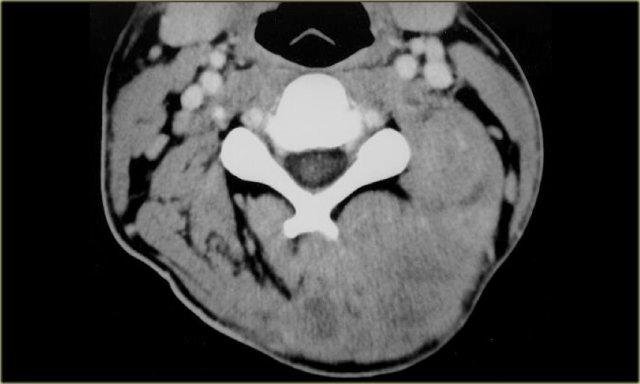

Paraganglioma: Siêu âm Doppler màu, MRI chuỗi xung T1W không tiêm thuốc tương phản từ và CT có tiêm thuốc cản quang

Paraganglioma (2)

Bên trái là hình ảnh của một bệnh nhân nữ 21 tuổi có khối ở bên phải.

Tổn thương này nằm giữa động mạch cảnh trong và động mạch cảnh ngoài, do đó là một khối u thần kinh.

Chẩn đoán phân biệt được giới hạn ở các khối u xuất phát từ dây thần kinh phế vị và đám rối giao cảm.

Trên CT và siêu âm Doppler màu, khối rõ ràng có tăng sinh mạch máu và chẩn đoán duy nhất có thể là paraganglioma.